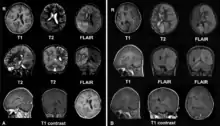

Left: December 2008, the patient was presented with headache and epilepsia partialis continua. There are lesions with local brain swelling in the right parietal and occipital lobes and right cerebellar hemisphere.

Right: April 2009, the same patient, now she is comatose with epilepsia partialis continua. There is progression of the encephalitis - the left cerebral hemisphere has been involved with severe brain swelling and shift of the midline structures.

The diagnosis may be made on the clinical features alone, along with tests to rule out other possible causes. An EEG will usually show the electrical features of epilepsy and slowing of brain activity in the affected hemisphere, and MRI brain scans will show gradual shrinkage of the affected hemisphere with signs of inflammation or scarring.[9]